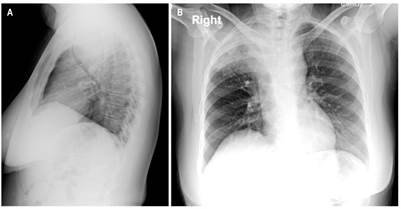

La paciente fue llevada a junta medicoquirúrgica por inquietudes acerca de los hallazgos histopatológicos, por lo que decidió llevar a biopsia nuevamente, esta vez por toracoscopia de la lesión mediastinal descrita que reportó un tumor fusocelular con inmunoperfil que favorece el tumor de vaina nerviosa periférica sin criterios claros de atipia celular (Figura 2) e inmunohistoquímica con positividad para proteína S100 y negatividad para leucemia mielógena aguda (LMA), H-Caldesmon, desmina, CD117, DOG-1, CD34, CKAE1/AE3 y STAT-6. El índice de proliferación celular (Ki-67) es del 5 %. Se concluyó que la masa corresponde a un schwannoma esofágico. Se realizó nueva TAC de tórax con contraste en la que se evidenció un aumento del tamaño de la masa con compromiso de la pleura mediastinal y el parénquima pulmonar apical derecho, en contacto con la arteria pulmonar derecha, el cayado aórtico y el cayado de la vena ácigos. Se presentó en junta quirúrgica nuevamente, con los servicios de cirugía de tórax, oncológica y esofágica, y se consideró que debido a la extensión, tamaño tumoral y compromiso vascular, el tumor se hace irresecable quirúrgicamente. Se derivó a oncología clínica para considerar otra opción terapéutica con el objetivo de aminorar los síntomas. Adicional al cuadro clínico descrito durante el transcurso de la patología, la paciente presentó episodios de neumonía que requirieron un manejo antibiótico y soporte ventilatorio de forma intrahospitalaria (Figura 3).

Figura 3 RX de tórax. Masa en el mediastino medio, con un componente aéreo interno en su aspecto superior que no descarta cavitación; esta imagen se comunica con consolidación adyacente del lóbulo superior derecho, lo cual no descarta un trayecto fistuloso. La masa genera un importante efecto compresivo sobre las estructuras adyacentes, especialmente sobre la tráquea, la cual disminuye su calibre en un 73 % aproximadamente. Masa con compromiso de la pleura mediastinal y el parénquima pulmonar apical derecho en contacto con la arteria pulmonar derecha, cayado aórtico y cayado de la vena ácigos sin signos de infiltración. A. Proyección lateral. B. Proyección posteroanterior.